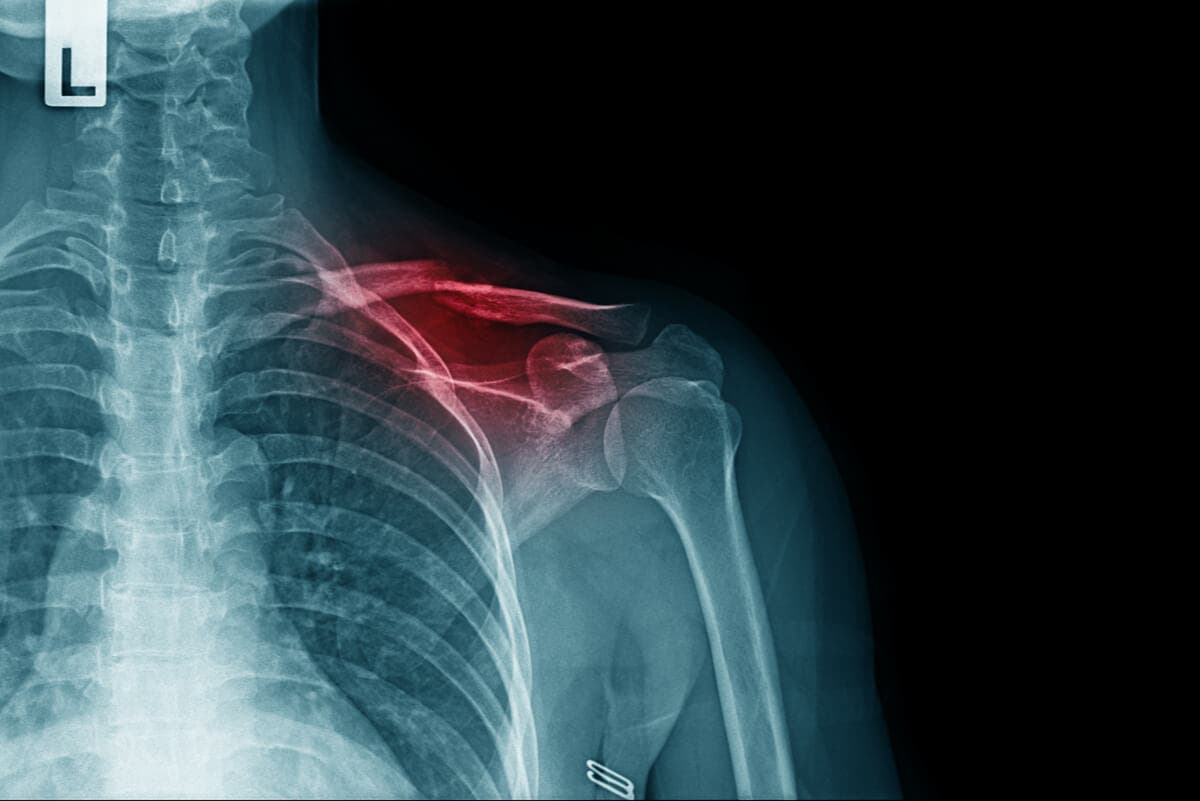

Una fractura de clavícula, como la que padece Mikel Landa por su caída en el Giro de Italia 2021, es una solución de continuidad en el hueso de la parte superior del tórax. Es decir, se trata de una interrupción en el recorrido natural que tiene el tejido óseo en esta zona.

La clavícula es una estructura anatómica que conecta el esternón con la escápula. De manera tradicional, se la divide en 3 segmentos para su estudio, considerando que las roturas pueden aparecer en la zona más cercana al cuello, en la más cercana al hombro o en la mitad.